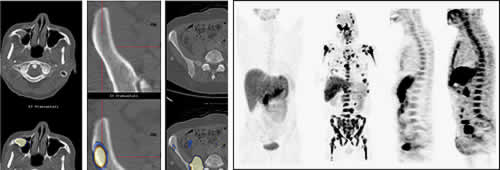

Der Einsatz bildgebender Verfahren dient an erster Stelle dem Nachweis von myelombedingten Knochen- und Knochenmarkveränderungen. Diese treten typischerweise in Form sogenannter Osteolysen (örtlich umschriebener Knochenauflösungszonen; Abbildung A) und fokaler Plasmazellansammlungen im Knochenmark auf (Abbildung 4B).

(Abbildung 4)

B) Darstellung von fokalen Läsionen in der Magnetresonanztomografie (MRT) der Wirbelsäule.

Ebenfalls häufig zeigt sich aber auch eine Osteoporose (diffuse Verminderung der Knochensubstanz) oder ein diffuser Befall des Knochenmarks.

Klassisches bildgebendes Verfahren war lange Zeit das konventionelle Röntgen zur Darstellung des Schädels, der Wirbelsäule, des Beckens sowie der langen Röhrenknochen (Oberarmknochen, Oberschenkelknochen), auch als "Pariser Schema" bezeichnet. Allerdings ist dieses Verfahren mit einer Reihe von Nachteilen bzw. Einschränkungen behaftet: Es ist relativ aufwendig und hat eine im Vergleich zu anderen Techniken schlechte Sensitivität (Empfindlichkeit). Darüber hinaus wird eine myelombedingte Knochenzerstörung oft erst sichtbar, wenn 30-50% der Knochensubstanz abgebaut ist. Aus diesem Grund kommen andere bildgebende Verfahren beim Multiplen Myelom bevorzugt zum Einsatz. Hierzu zählen die Computertomografie (CT), die sich besonders zur Beurteilung von Knochensubstanz bei Verdacht auf eine Instabilität des Knochens mit drohender Bruchgefahr (z.B. von Wirbelkörpern) eignet und die Magnetresonanztomografie (MRT), die besonders gut die nicht knöchernen Gewebe (z.B. Nervenstränge und Knochenmark) abbildet.

Der Stellenwert der kombinierten PET/CT (PET = Positronenemissionstomografie), siehe Abbildung 5, wird bereits seit mehreren Jahren untersucht. Diese Untersuchungstechnik ist allerdings weiterhin kein Routineverfahren in der Diagnostik des Multiplen Myeloms.

(Abbildung 5)

Die PET ist ein Verfahren, welches auf der gesteigerten Stoffwechselaktivität von Tumorzellen beruht (rechts). Kombiniert wird die PET mit einem Verfahren zur Darstellung der Knochensubstanz (CT; links), wodurch eine Abbildung von Myelomherden im Knochenmark und außerhalb des Knochenmarks möglich wird.